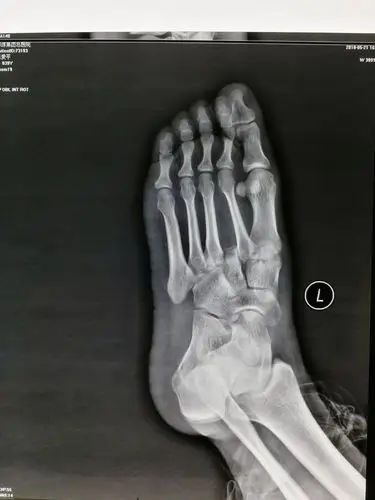

患者,女,39岁,从一米高处摔下,诊断,左足lisfranc损伤,请教入路,固定